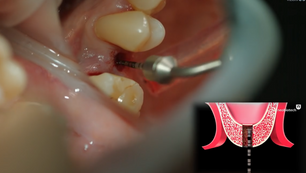

Sinus graft procedure in the crestal approach

Pre-operative Observation Post-operative observation

Dr. Pavel Yaroshevich

Mar 10, 20161 min read